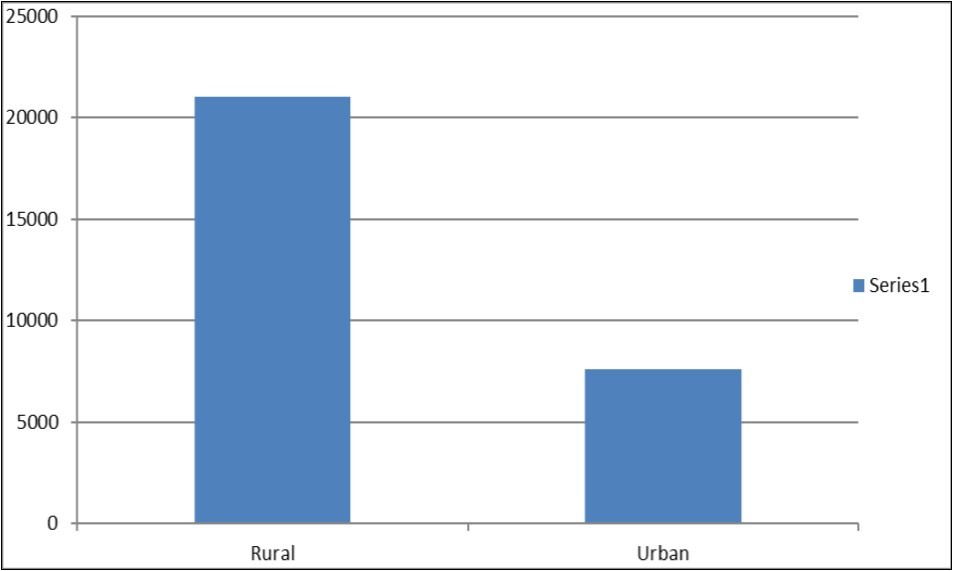

From Figure 1 below, we can see that there are more deaths in the rural area than in the urban area. The reason for this increase is the fact that children suffer from social infrastructure and services like (schools, roads, electricity, and health services). Some other identifiable cause of child mortality can also occur from parent unemployment, social deprivation, and endemic conflict, in the rural area than in the urban area.

Figure 1.Data Analysis-Rural Urban Differential